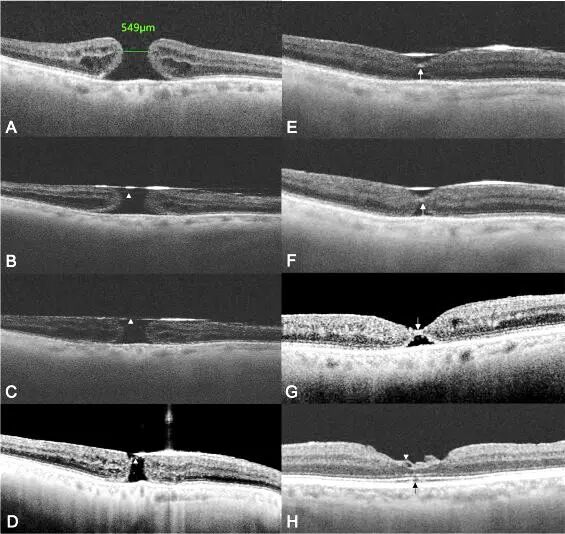

图3 全域扫频OCT下黄斑裂孔ILM瓣翻转覆盖术后早期形态学愈合过程。A. 术前全层黄斑裂孔。B. 术后5分钟,气液平面下ILM瓣在位。C. 术后俯卧1h。D. 俯卧24h后,孔径显著减小,ILM瓣在位,孔缘可见少许高反射增生组织。E. 术后48h, 裂孔处桥接组织清晰可见。F术后1周,视网膜外层缺损进一步减小。G术后1月,眼内气体吸收,高反射桥接组织清晰可见,并可观察到ELM开始重建。H. 术后2月,裂孔完全愈合,皱褶的ILM瓣留存在视网膜表面,ELM已恢复,仍可见椭圆体带一极小缺损(黑箭头)。

图4 黄斑裂孔(双)晕环征。A. 近红外眼底成像,裂孔周围可见清晰的外圈高反射环(白箭头)和内部低反射晕环(黑箭头)。B. 眼底自发荧光(FAF)。C. 术前全域扫频OCT显示裂孔缘外椭圆体带缺损,孔缘处上翘,视网膜层间囊样改变,与眼底成像和自发荧光双环对应。D. ILM瓣翻转覆盖术后5分钟, ILM瓣覆盖于裂孔表面。E. 术后俯卧位1h后,孔径明显缩小。ILM瓣在位。F与G. 术后24h及1周,黄斑裂孔完全解剖学闭合。裂孔区域被跨越视网膜层的高反射物质填充。H与I. 术后1个月及3个月,外层视网膜仍存在缺损(白三角)。